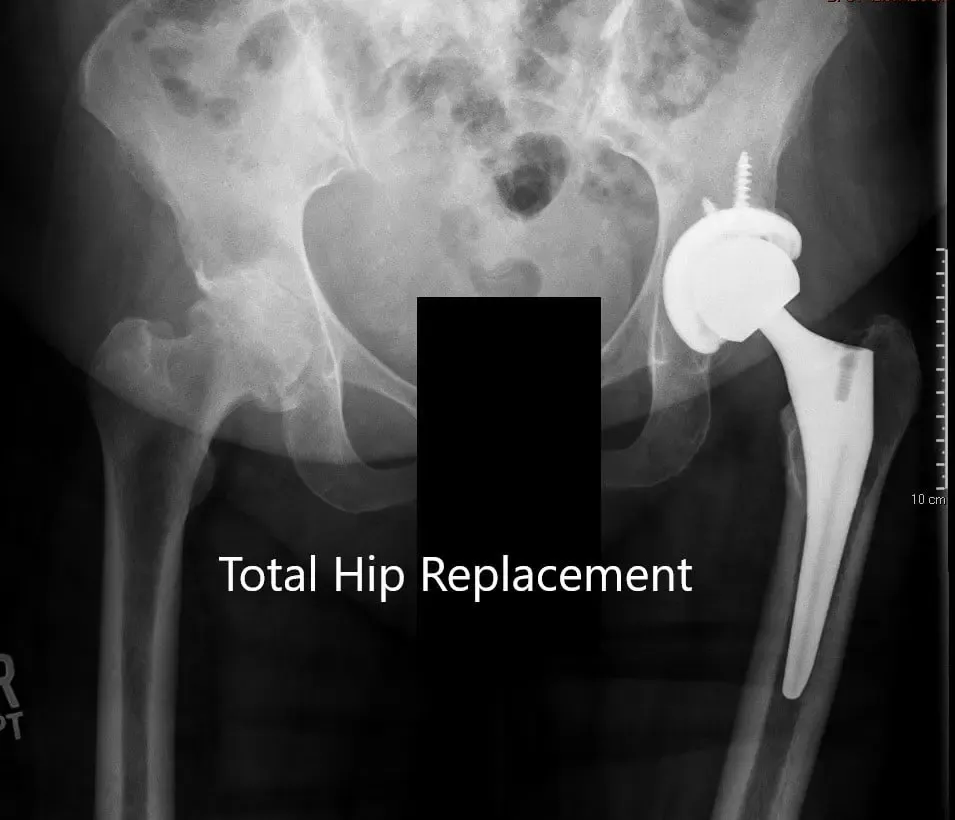

Radiografía postoperatoria que muestra la vista AP de la pelvis y la vista lateral de la cadera izquierda.

OPERACIÓN: Artroplastia total de cadera izquierda usando cabeza femoral cerámica de 36 mm más 5 con un sistema de tallo de cuello de 127 grados tamaño 5 con un agujero de racimo de concha acetabular de 54 mm con inserto de polietileno con dos tornillos.